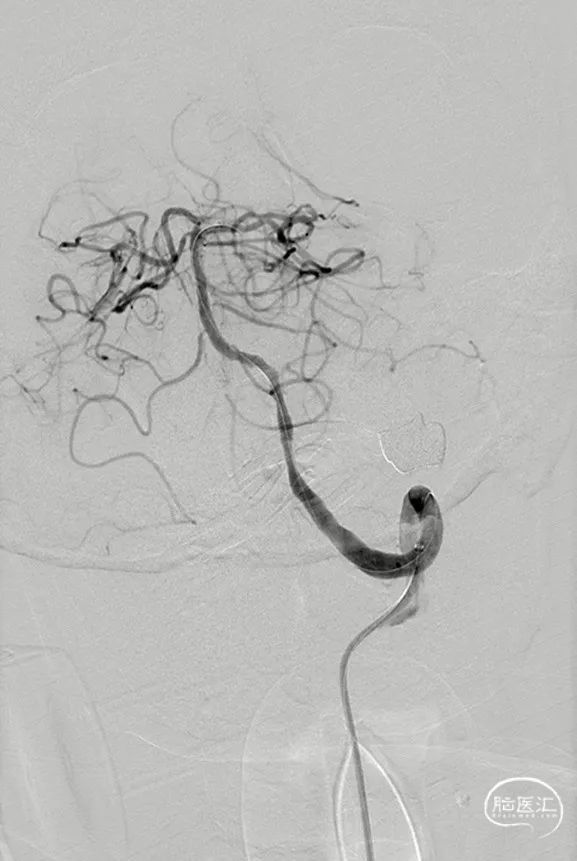

球囊到位

3mm*20mm球囊扩张

复查造影

5min后复查造影

XT27微导管到位

支架导管到位

支架到位

回撤支架输送杆

4.5mm*20mm自膨支架释放